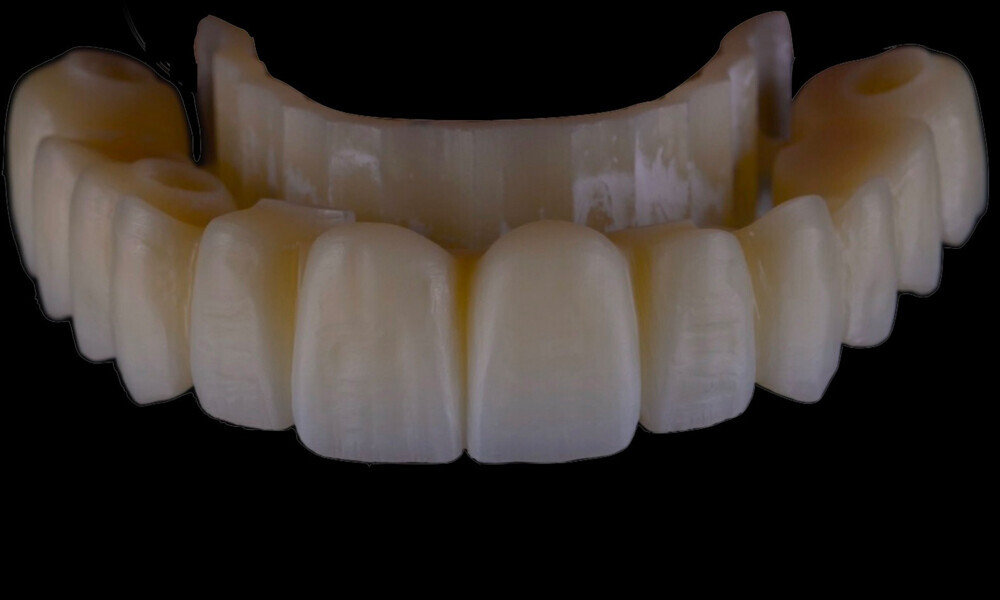

Employing a fully guided surgical protocol alongside a completely digital prosthetic workflow allowed for the precise design and milling of a PMMA provisional prosthesis (Figs. 34 & 35). The implant loading protocol implemented was immediate loading with equal distribution of forces across the entire prosthesis. The patient received the screw-retained provisional prosthesis on the same day. Temporary abutments (titanium copings) were placed on top of the screw-retained abutments. The spaces between the titanium copings and the provisional prosthesis were filled (Figs. 36–38). Any excess material was cut away, and the provisional prosthesis was subsequently polished to ensure a smooth finish (Fig. 39). The provisional prosthesis was then attached and securely fixed to the titanium copings to a 15 N cm torque (Fig. 40). Oral hygiene instructions were provided, and the occlusion was assessed (Figs. 41 & 42). A final control radiograph was obtained and confirmed that all parameters were within normal limits (Fig. 43).

Four months later, we proceeded with the final prosthetic procedure based on clinical and radiographic evidence confirming osseointegration. The case was completed using Straumann RevEX scan bodies for a full monolithic design with a completely digital workflow. First, an intra-oral scan of the opposite arch was taken, followed by an intra-oral scan with the screwed-in temporary abutments. An intra-oral bite scan and an intra-oral scan of the soft tissue with the screw-retained abutments in place were then taken. The reverse scan bodies were attached to the provisional prosthesis, which was scanned extra-orally. Next, the prototype and verification jig were designed, followed by the milling of the prototype and verification jig (Figs. 45 & 46).

During the next visit, the milled prototype and verification jig were tried in, and the design and manufacturing of the final prosthesis were completed (Figs. 47 & 48). The final abutment utilised was Variobase for bridge (Straumann), placed on top of the screw-retained abutments. The material chosen for the final prosthesis was monolithic zirconia (Figs. 49 & 50).